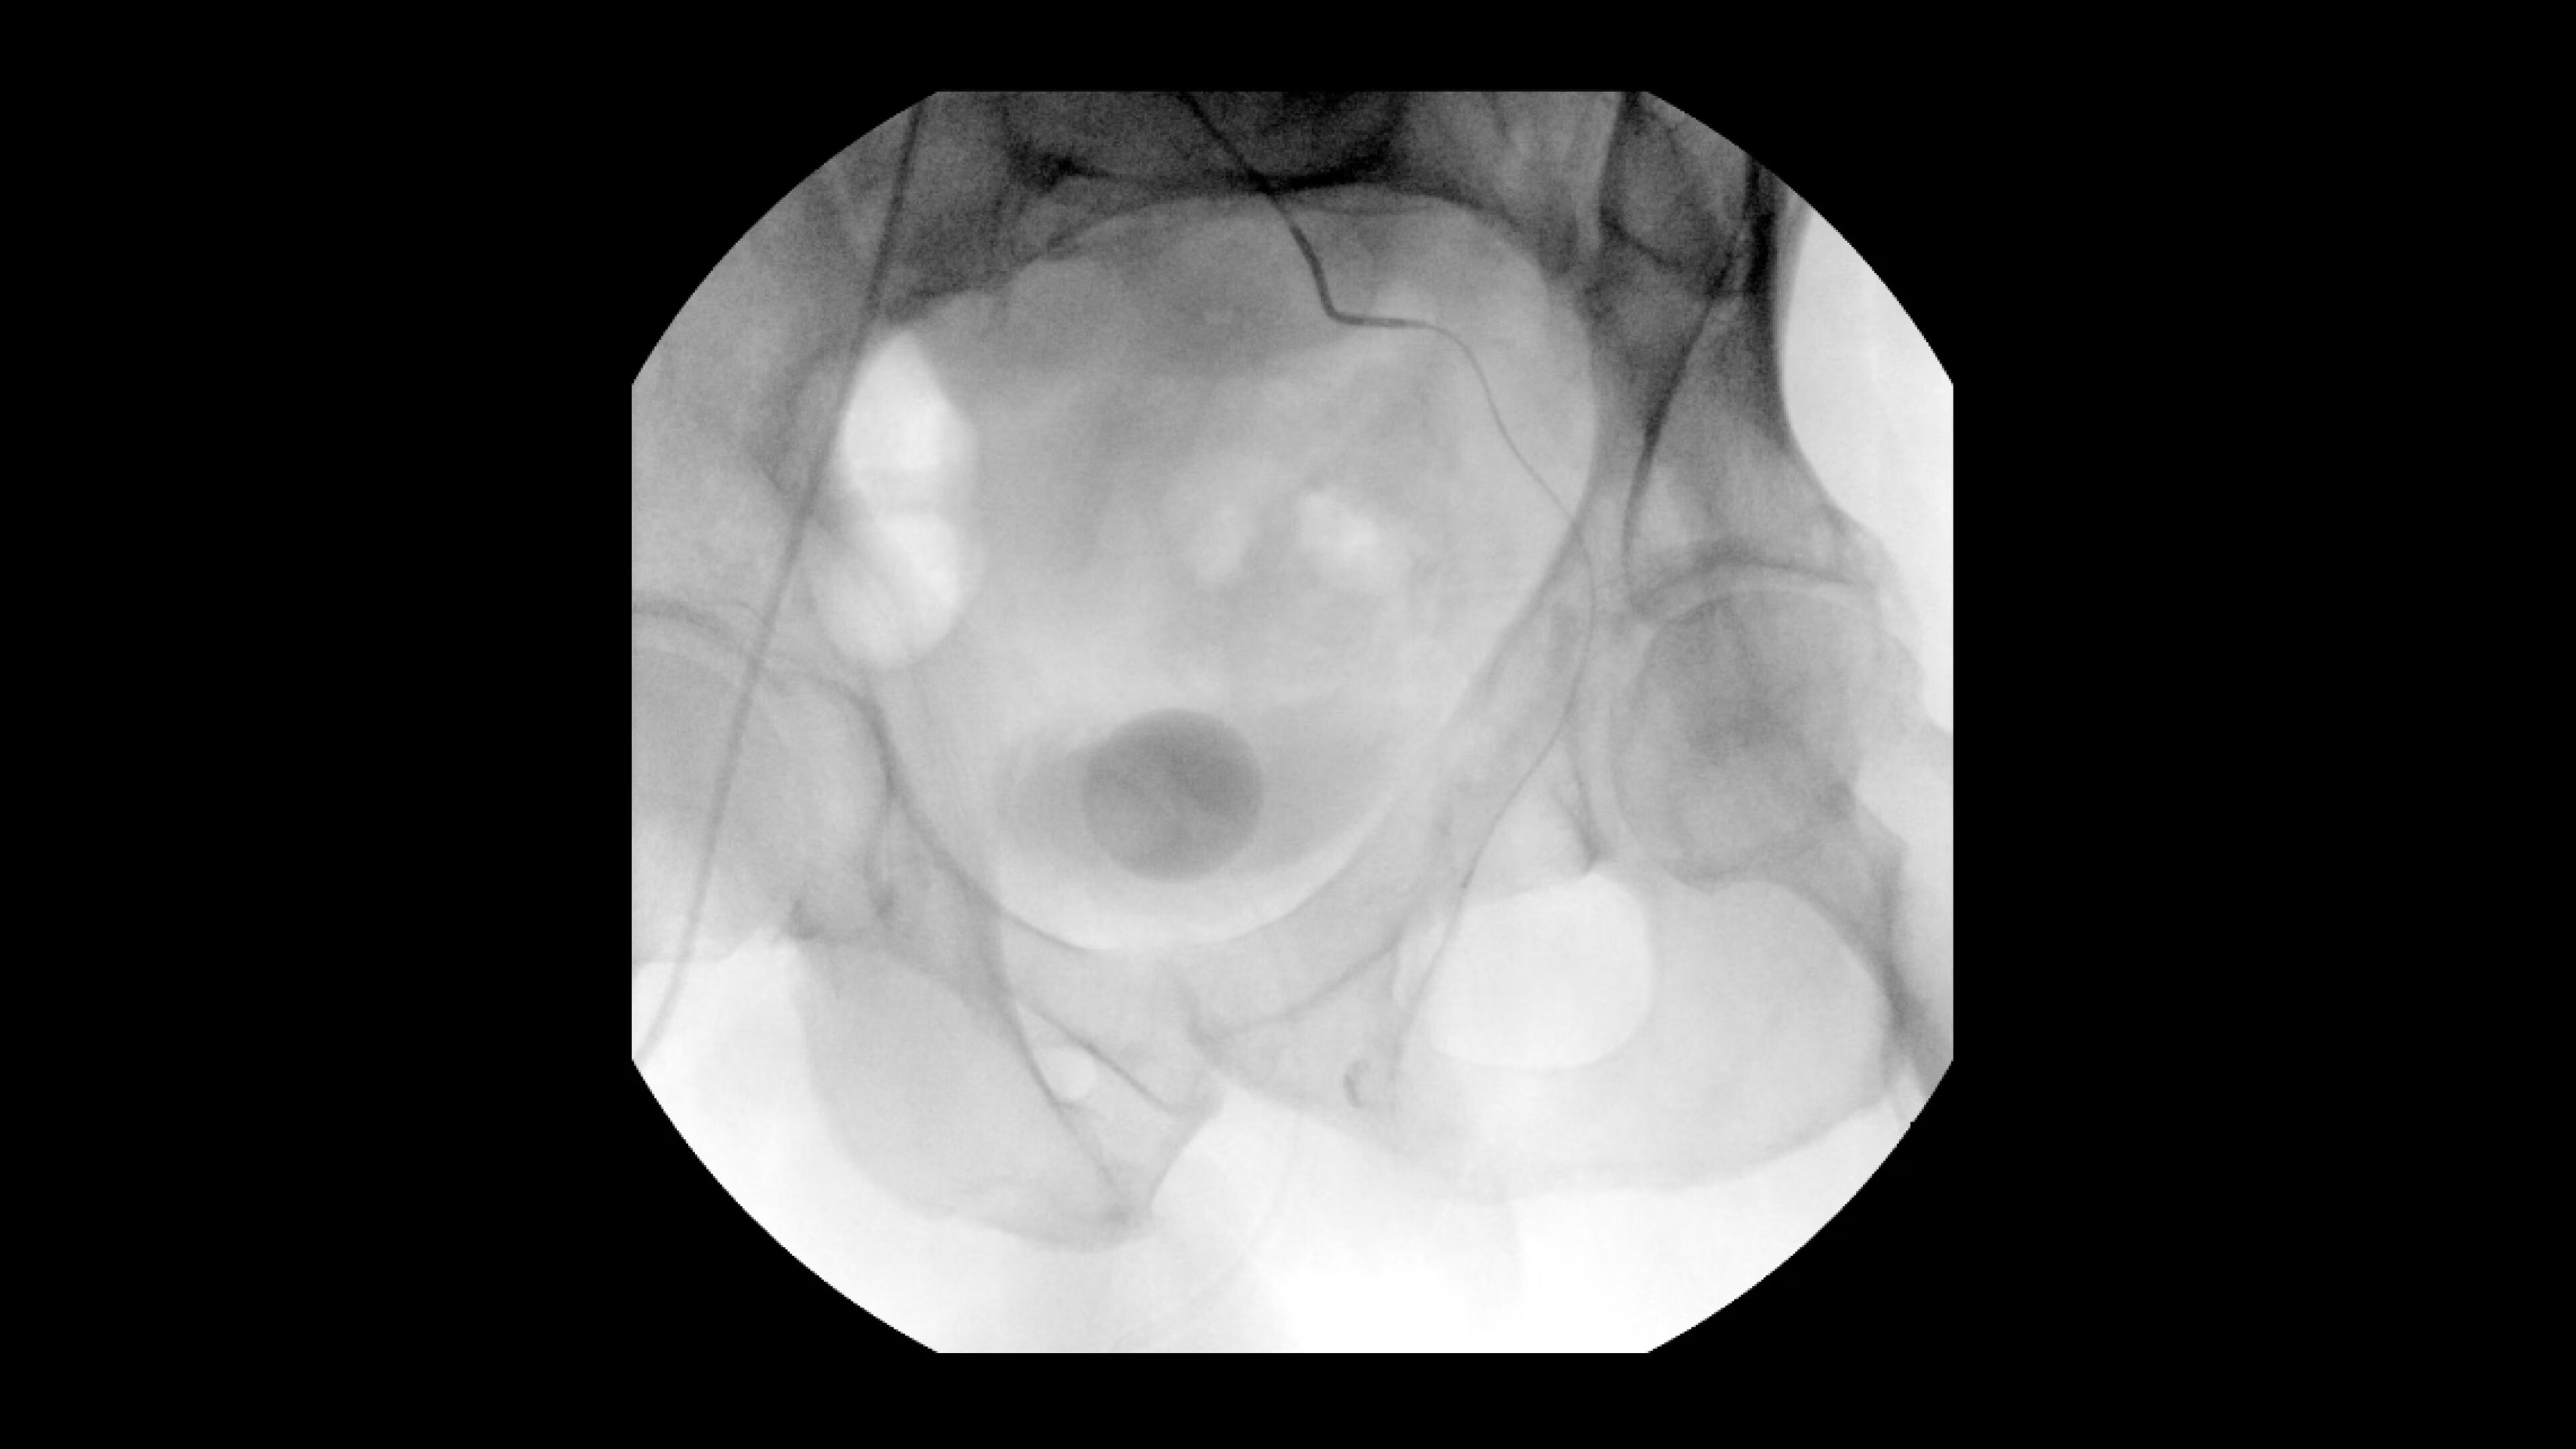

Interventional imaging you need

Interventional procedures require powerful imaging systems. OEC premium

C-arms perform in a variety of procedures such as:

• Prostatic Artery Embolization (PAE)

• Uterine artery embolization

• Pelvic congestion treatments

• Genicular artery embolization

• Venous leak embolization

*Based on GE HealthCare study of OEC 3D imaging results with application of enhanced noise reduction algorithm